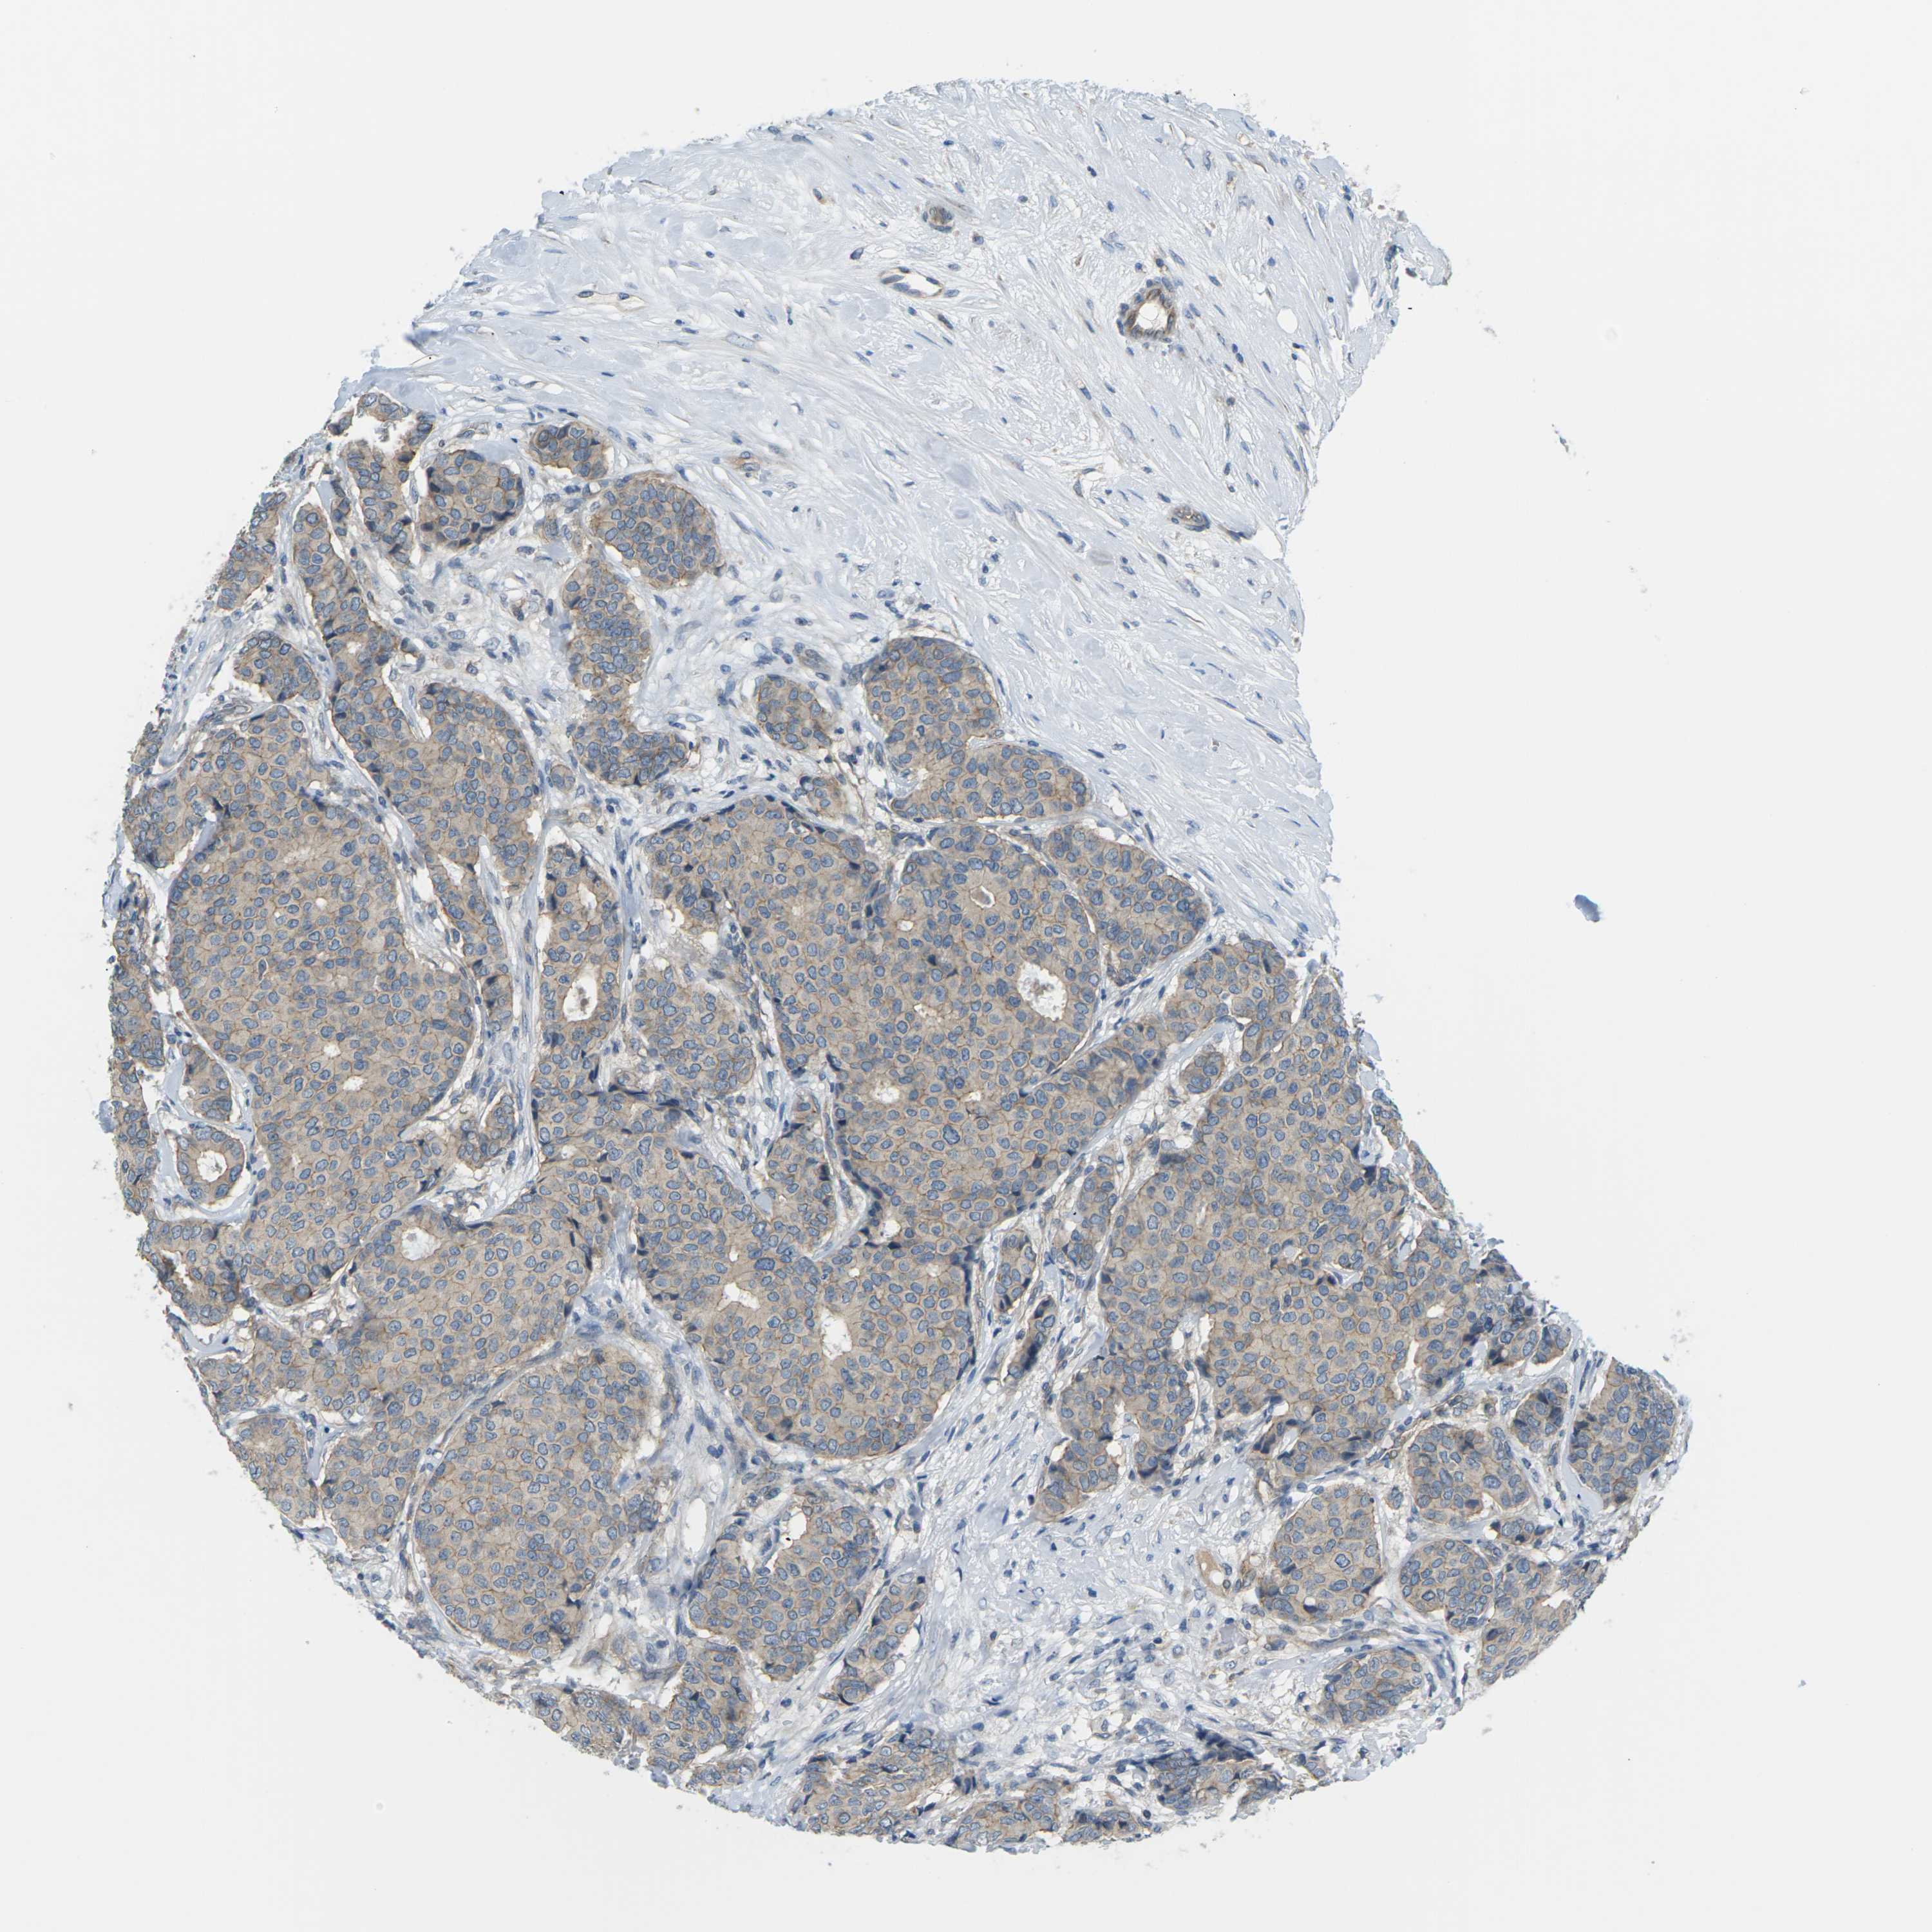

BRCA TCGA BRCA VALIDATION PROTEIN EXPRESSION